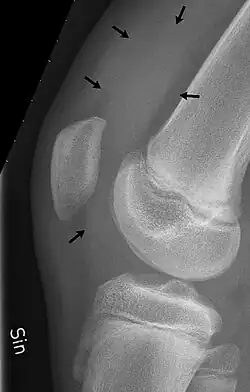

X-ray of the knee of a 12-year-old male, showing knee effusion of medium severity, marked by black arrows. It displaces the patella anteriorly and extends into the suprapatellar bursa.

X-Ray

An X-ray may be recommended by your provider as a way to obtain a 2-dimensional image to visualize the joint in question. In the presence of trauma an X-ray can be especially useful to verify that there is no break, dislocation, or deformity. In an atraumatic knee, an X-Ray can be used to identify or rule out other causes of a knee infusion including some inflammatory or age-related causes.